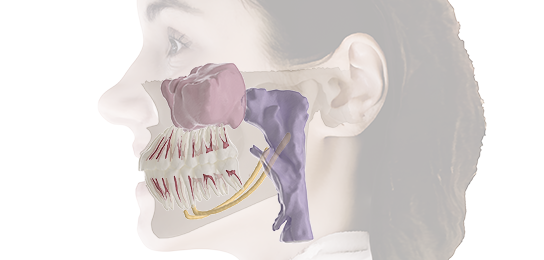

5D is a clinical imaging solution that combines CBCT data and facial data to create an anatomical patient model. Using intelligent technology, it automatically aligns CBCT data and segments anatomical structures to generate 5D images. This enables digital treatment and diagnosis based on accurate and intuitive data.

5D Solution

5D is a clinical imaging solution that combines CBCT data and facial data to create an anatomical patient model. Using intelligent technology, it automatically aligns CBCT data and segments anatomical structures to generate 5D images. This enables digital treatment and diagnosis based on accurate and intuitive data.